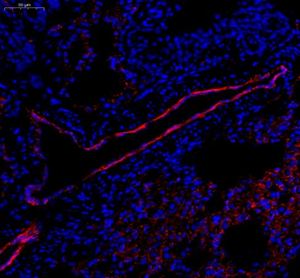

| IF analysis of CD31 (GB12063). Sample: Mouse lung (Paraffin), 4% PFA (G1101) 12-24h. Antigen retrieval: Citrate buffer (pH 6.0) (G1201), pressure cooker 2min. Blocking buffer: 3% BSA in PBS (GC305010), RT, 30min. Primary antibody: 1: 600, 4°C overnight. Secondary antibody: Cy3 conjugated Goat Anti-mouse IgG (H+L)(GB21301),1: 200 RT 1h. |

| IF analysis of CD31 (GB12063). Sample: Mouse lung (Paraffin), 4% PFA (G1101) 12-24h. Antigen retrieval: Citrate buffer (pH 6.0) (G1201), pressure cooker 2min. Blocking buffer: 3% BSA in PBS (GC305010), RT, 30min. Primary antibody: 1: 600, 4°C overnight. Secondary antibody: Cy3 conjugated Goat Anti-mouse IgG (H+L)(GB21301),1: 200 RT 1h. |